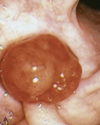

GIST

presentation of GIST

asymptomatic

sx due to mass effect when large, may ulcerate causing bleeding